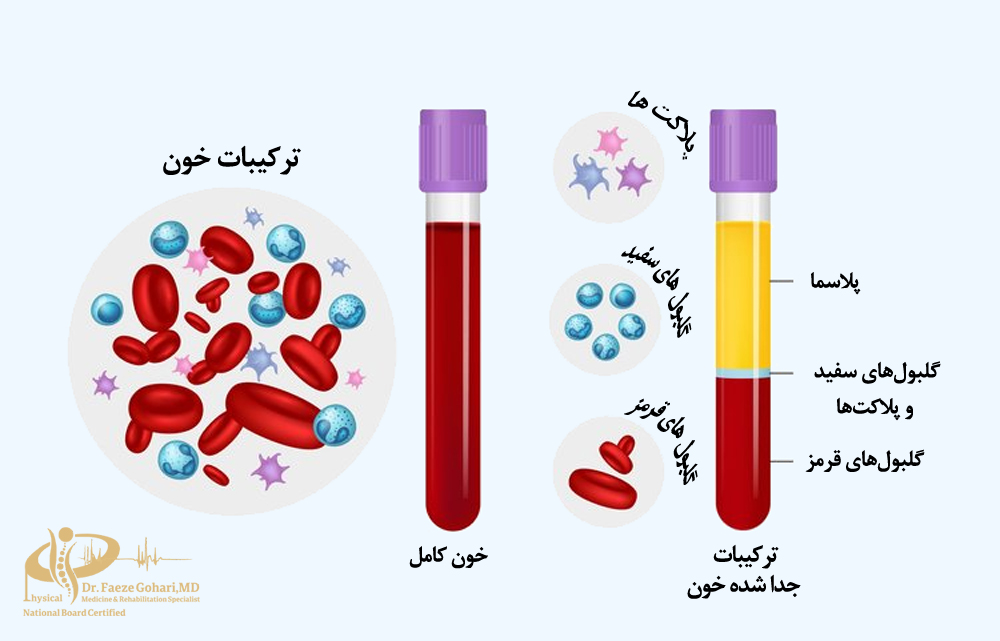

خونگیری

ابتدا مقدار مشخصی از خون بیمار (معمولاً بین ۱۵ تا ۳۰ میلیلیتر) از طریق ورید بازو گرفته میشود. این خون پایهای برای تهیه پیآرپی خواهد بود.

تهیه پی آر پی

خون گرفتهشده بلافاصله در دستگاه سانتریفیوژ قرار میگیرد تا پلاکتها از سایر اجزای خون جدا شوند. این فرایند معمولاً در دو مرحله انجام میشود تا پیآرپی با غلظت بالای پلاکت و حداقل ناخالصی به دست آید. همچنین، نوع و غلظت نهایی PRP بسته به نوع آسیب میتواند شخصیسازی شود؛ برای مثال، در برخی موارد از فرمهای دارای گلبول سفید و در موارد دیگر از فرمهای بدون آن استفاده میشود تا با نیاز درمانی بیمار هماهنگ باشد.

غلظت پلاکتها باید ۴ تا ۶ برابر بیشتر از پلاسمای معمولی باشد. این غلظت به پزشک کمک میکند تا حداکثر اثربخشی را برای بهبود بافتها ارائه دهد.